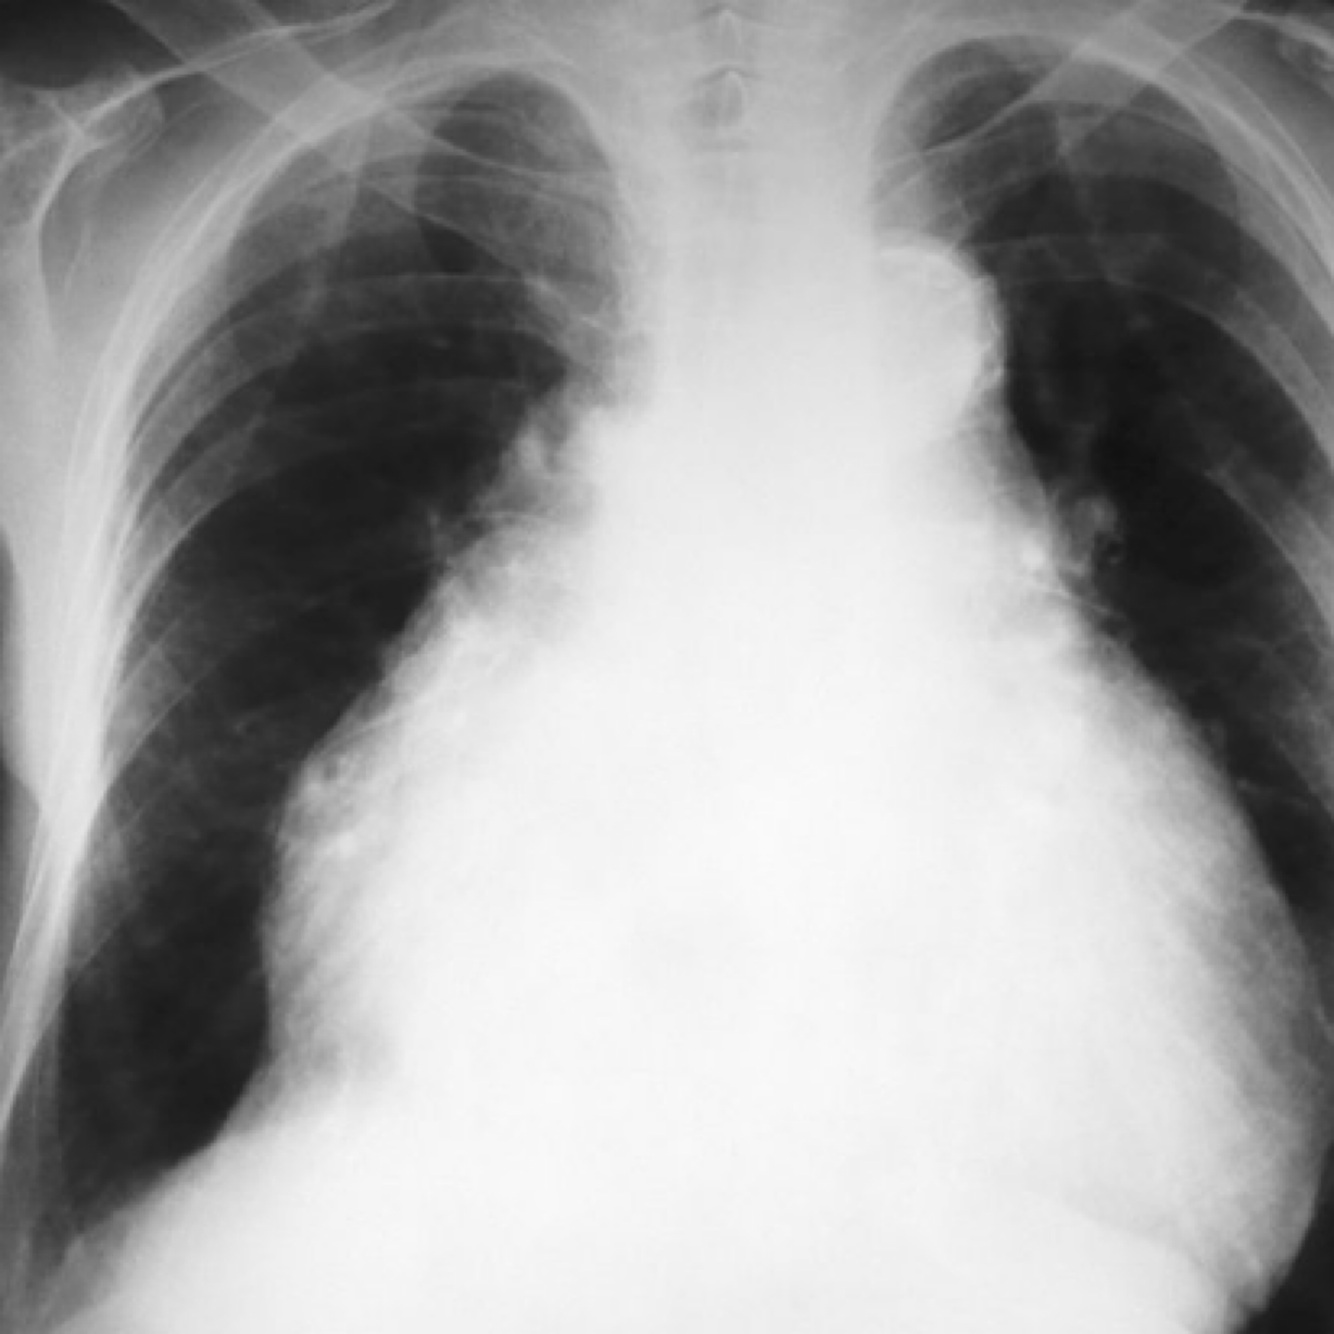

right pleural effusion shown on x-ray,